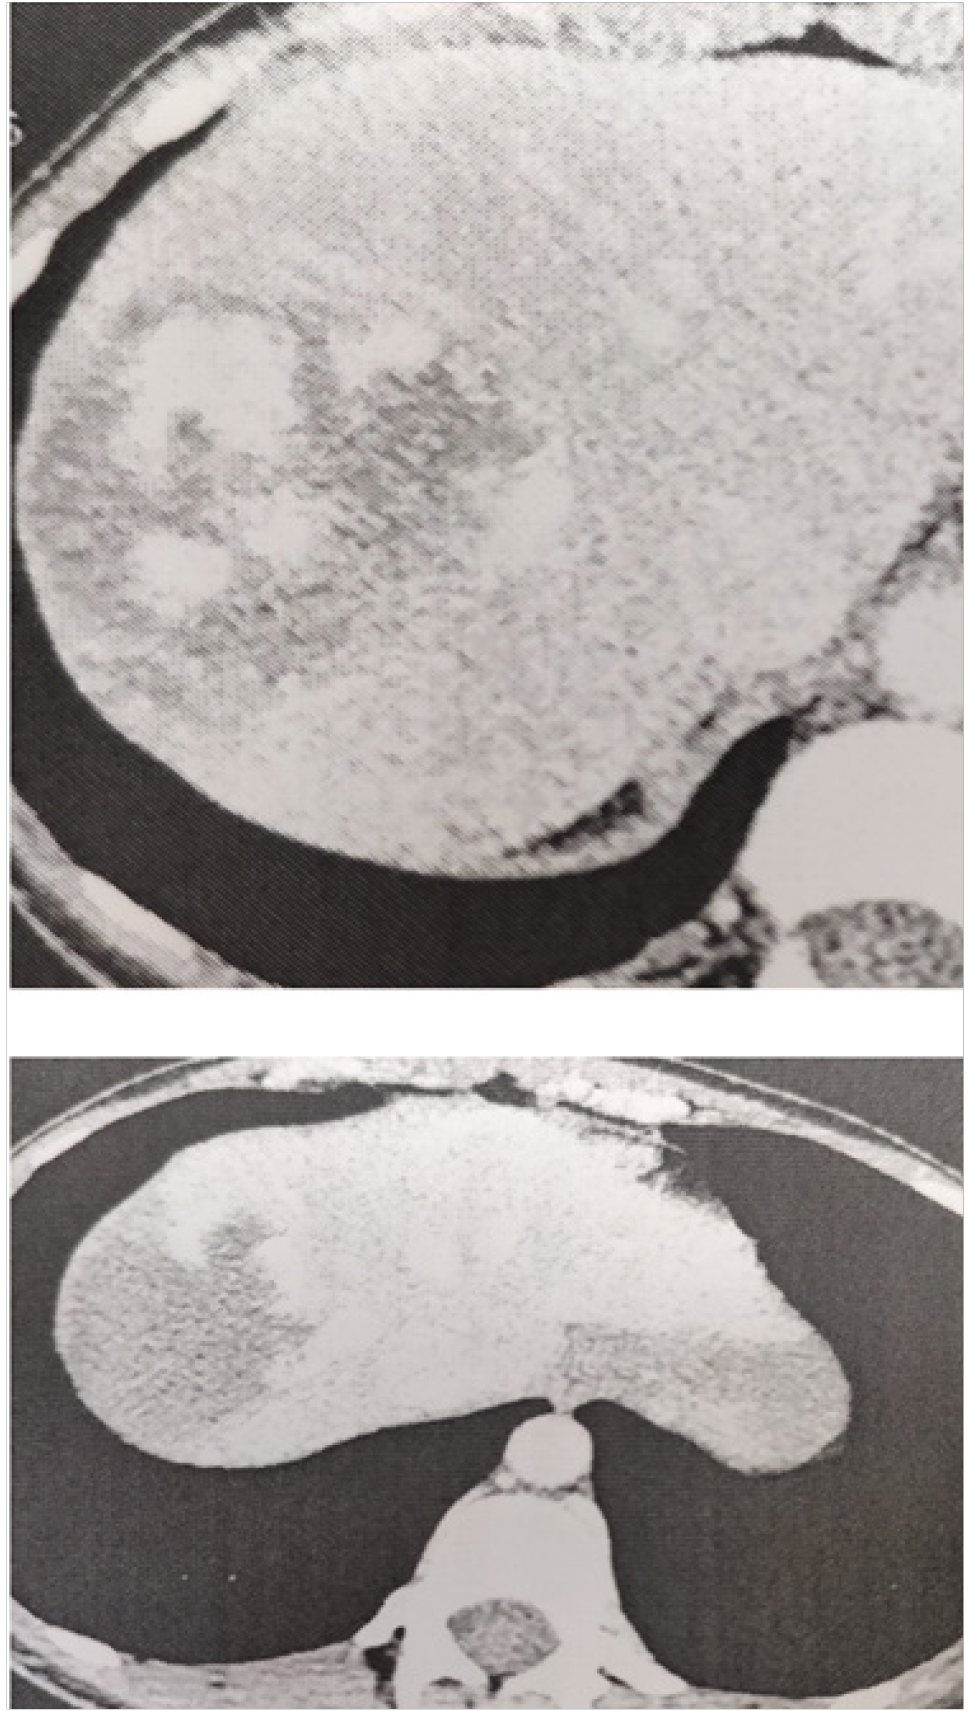

Представляем клинический случай лечения пациентки 1985 года рождения, которая обратилась в консультативную поликлинику ККБСМП имени М.А. Под- горбунского в июне 2019 г. При осмотре пациентка предъявляла жалобы на постоянный дискомфорт в эпигастрии, правом подреберье, тошноту, одышку. Больная амбулаторно наблюдается по поводу гемангиом печени, периодически выполняет УЗИ органов брюшной полости в динамике, тогда максимальный размер их достигал 2,5–3 см. При объективном осмотре состояние пациентки легкой степени тяжести. Кожные покровы телесного цвета. Дыхание везикулярное, хрипов нет, ЧДД 18 в минуту. Гемодинамика стабильная. Живот симметричный, участвует в акте дыхания, не вздут, при пальпации безболезненный во всех отделах, объемных образований, инфильтратов не пальпируются. Перитонеальные симптомы отрицательные. Стул ежедневный, диурез не нарушен. По данным последнего ультразвукового исследования в проекции в проекции 6–7 сегментов печени имеется гемангиома 8 см в максимальном диаметре, в проекции 8 сегмента печени гемангиома 2 см в максимальном диаметре измерения. Больная была госпитализирована в отделение. При обследовании результаты общего анализа крови, общего анализа мочи, биохимического анализа крови, коагулограммы крови в норме. Фиброгастродуоденоскопия, фиброколоноскопия без органической патологии. Выполнено ультразвуковое исследование и компьютерная томография с болюсным контрастированием органов брюшной полости, по результатам которых печень расположена обычно, краниокаудальный размер печени 157 мм, контуры четкие, ровные, портальной и билиарной гипертензии нет, в проекции 7-го сегмента печени имеется объемное образование до 8 см в размерах, тесно прилегает к правой печеночной вене, рядом расположены еще 2 образования до 2,5 см, также имеется образование до 2 см в проекции S4 и до 4 см в S3 печени, тип контрастирования образований характерен для гемангиом (рис. 1). Выполнена КТ-волюмометрия паренхимы печени, объем которой составляет 1500 см³, объем гемангиом 190 см³, объем интактной паренхимы печени (1, 2, 3, 4-й сегменты печени) 250 см³.

Протокол операции. Под эндотрахеальным наркозом лапаротомия по Кальне. При ревизии левая доля с признаками гипертрофии, достаточных размеров, расценена как достаточная для обеспечения функции после резекции правой доли печени (рис. 3).